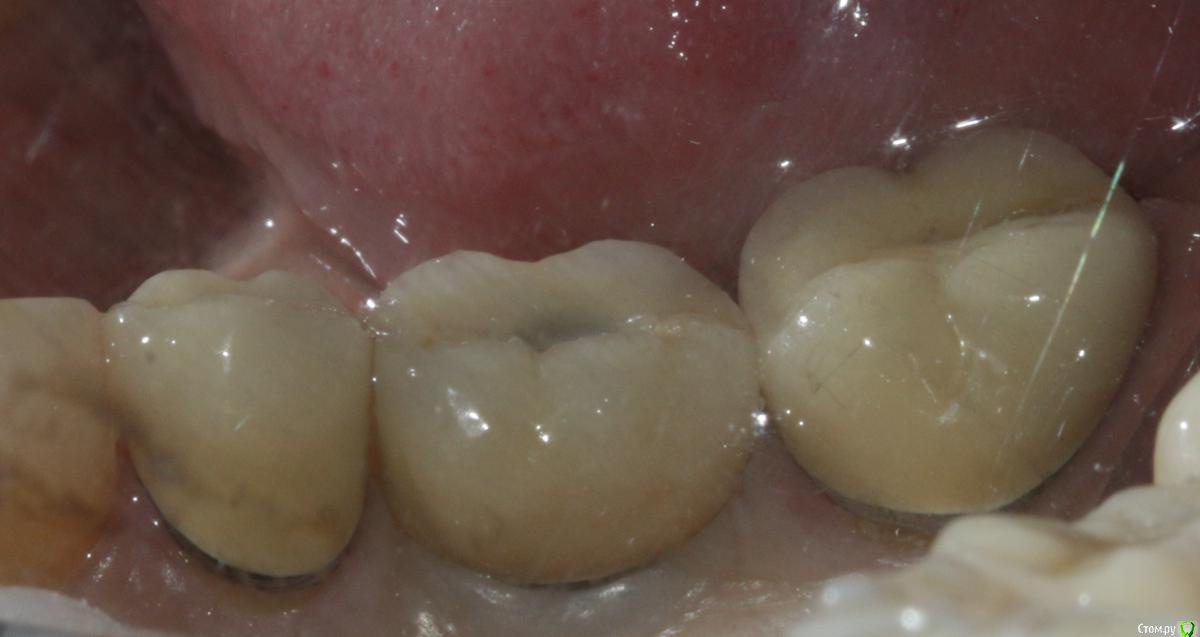

Ильдар Опубликовано 29 марта, 2015 Поделиться Опубликовано 29 марта, 2015 Коллеги, здравствуйте!Вот демонтировал старье. мк на зубы.имплант 4310, поставил поглубже.мк на имплант - техник прислал коронку с шахтой и абатмент,я склеил на fuji1. закрутил на 35 н.залепил не очень красиво , но с плавиковой, силаном и олбонд 3. думаю надежно.контрольный прицельный есть, видимо забыл его. извиняюсь за нечеткие fото. буду рад отзывам 3 Ссылка на комментарий

k.t.m. Опубликовано 29 марта, 2015 Поделиться Опубликовано 29 марта, 2015 все нра и прилегание коронок на зубах и витальность, но вот дентиум больше 1мм не стал бы заглублять,при отсроченном протоколе.и для одиночек снимаю закрытым методом-меньше возни 1 Ссылка на комментарий

Ильдар Опубликовано 30 марта, 2015 Автор Поделиться Опубликовано 30 марта, 2015 а зачем?Видимый металл на 6-м это не абатмент, это гирлянда. Граница коронка /абатмент глубже. Поэтому винтовая. Ссылка на комментарий

Nemiroff Опубликовано 12 апреля, 2015 Поделиться Опубликовано 12 апреля, 2015 (изменено) в каталоге дентиум написано, что абатменты фиксируются усилием 25-30 ньютон. при большем усилии, если вы будете пытаться открутиться с конусной системы, то имеете высокий риск сломать винт, сорвать шахту винта или просто не открутить ничего. показаний к заглублению в данном клиническом случае нет на мой взгляд.а показания к круговой гирлянде не соседних зубах заключались в их витальности и необходимости сделать тонкий переход края коронки в тонкий уступ? Изменено 12 апреля, 2015 пользователем Nemiroff Ссылка на комментарий

Dr.Sham Опубликовано 15 апреля, 2015 Поделиться Опубликовано 15 апреля, 2015 МК вообще должна быть либо по кругу с гирляндой, либо с плечом. Ссылка на комментарий